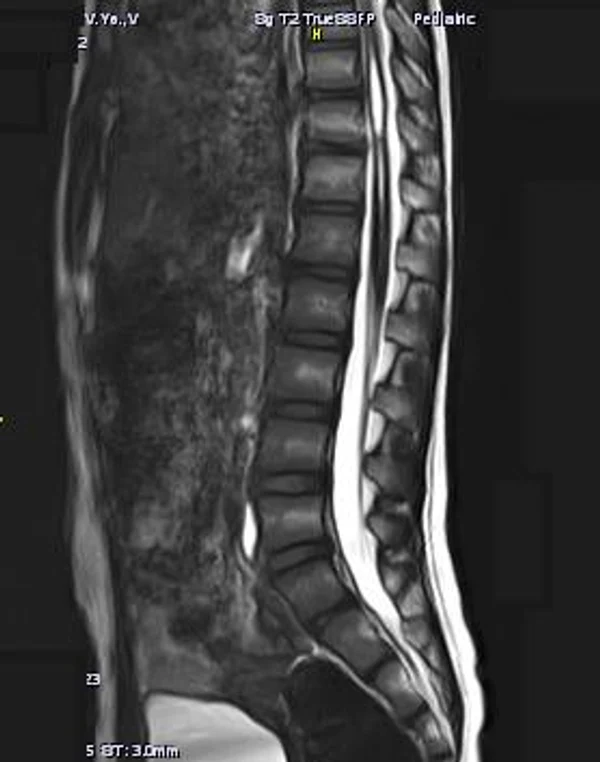

Spina bifida, спинно-мозговые грыжи, диастематомиелия, липоменингомиелолоцеле, фиксированный спинной мозгSpina bifida включают различные типы нарушения закладки и развития нервной трубки на спинальном уровне, что сопровождается незаращением дужек позвоночника и часто сопровождается одновременным пороком развития спинного мозга и его оболочек. Встречаются у 1 на 1000 – 3000 новорожденных. Могут наблюдаться в различных отделах позвоночника, но наиболее часто встречается в пояснично-крестцовом отделе. Незаращение дужек позвонков с наличием грыжевого выпячивания обозначается в литературе по разному: спинно-мозговые грыжи, spina bifida, spina bifida cystica, spina bifida vera, spina bifida typica, spina bifida aperta. Классификация spina bifida aperta: I Рахишизис. II Спинномозговые грыжи. Менингоцеле. Менингорадикулоцеле. Миеломенингоцеле. Миелоцистоцеле. Липоменингомиелоцеле. Основные сопутствующие пороки центральной нервной системы: Гидроцефалия до 65-85%. Аномалия Киари 2. Сирингомиелия.